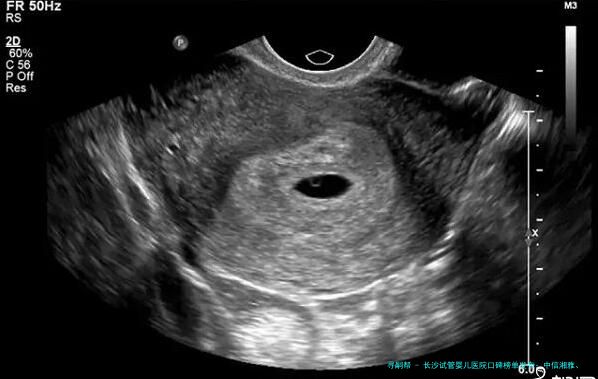

阴道B超下采卵术8000500065006000-7000